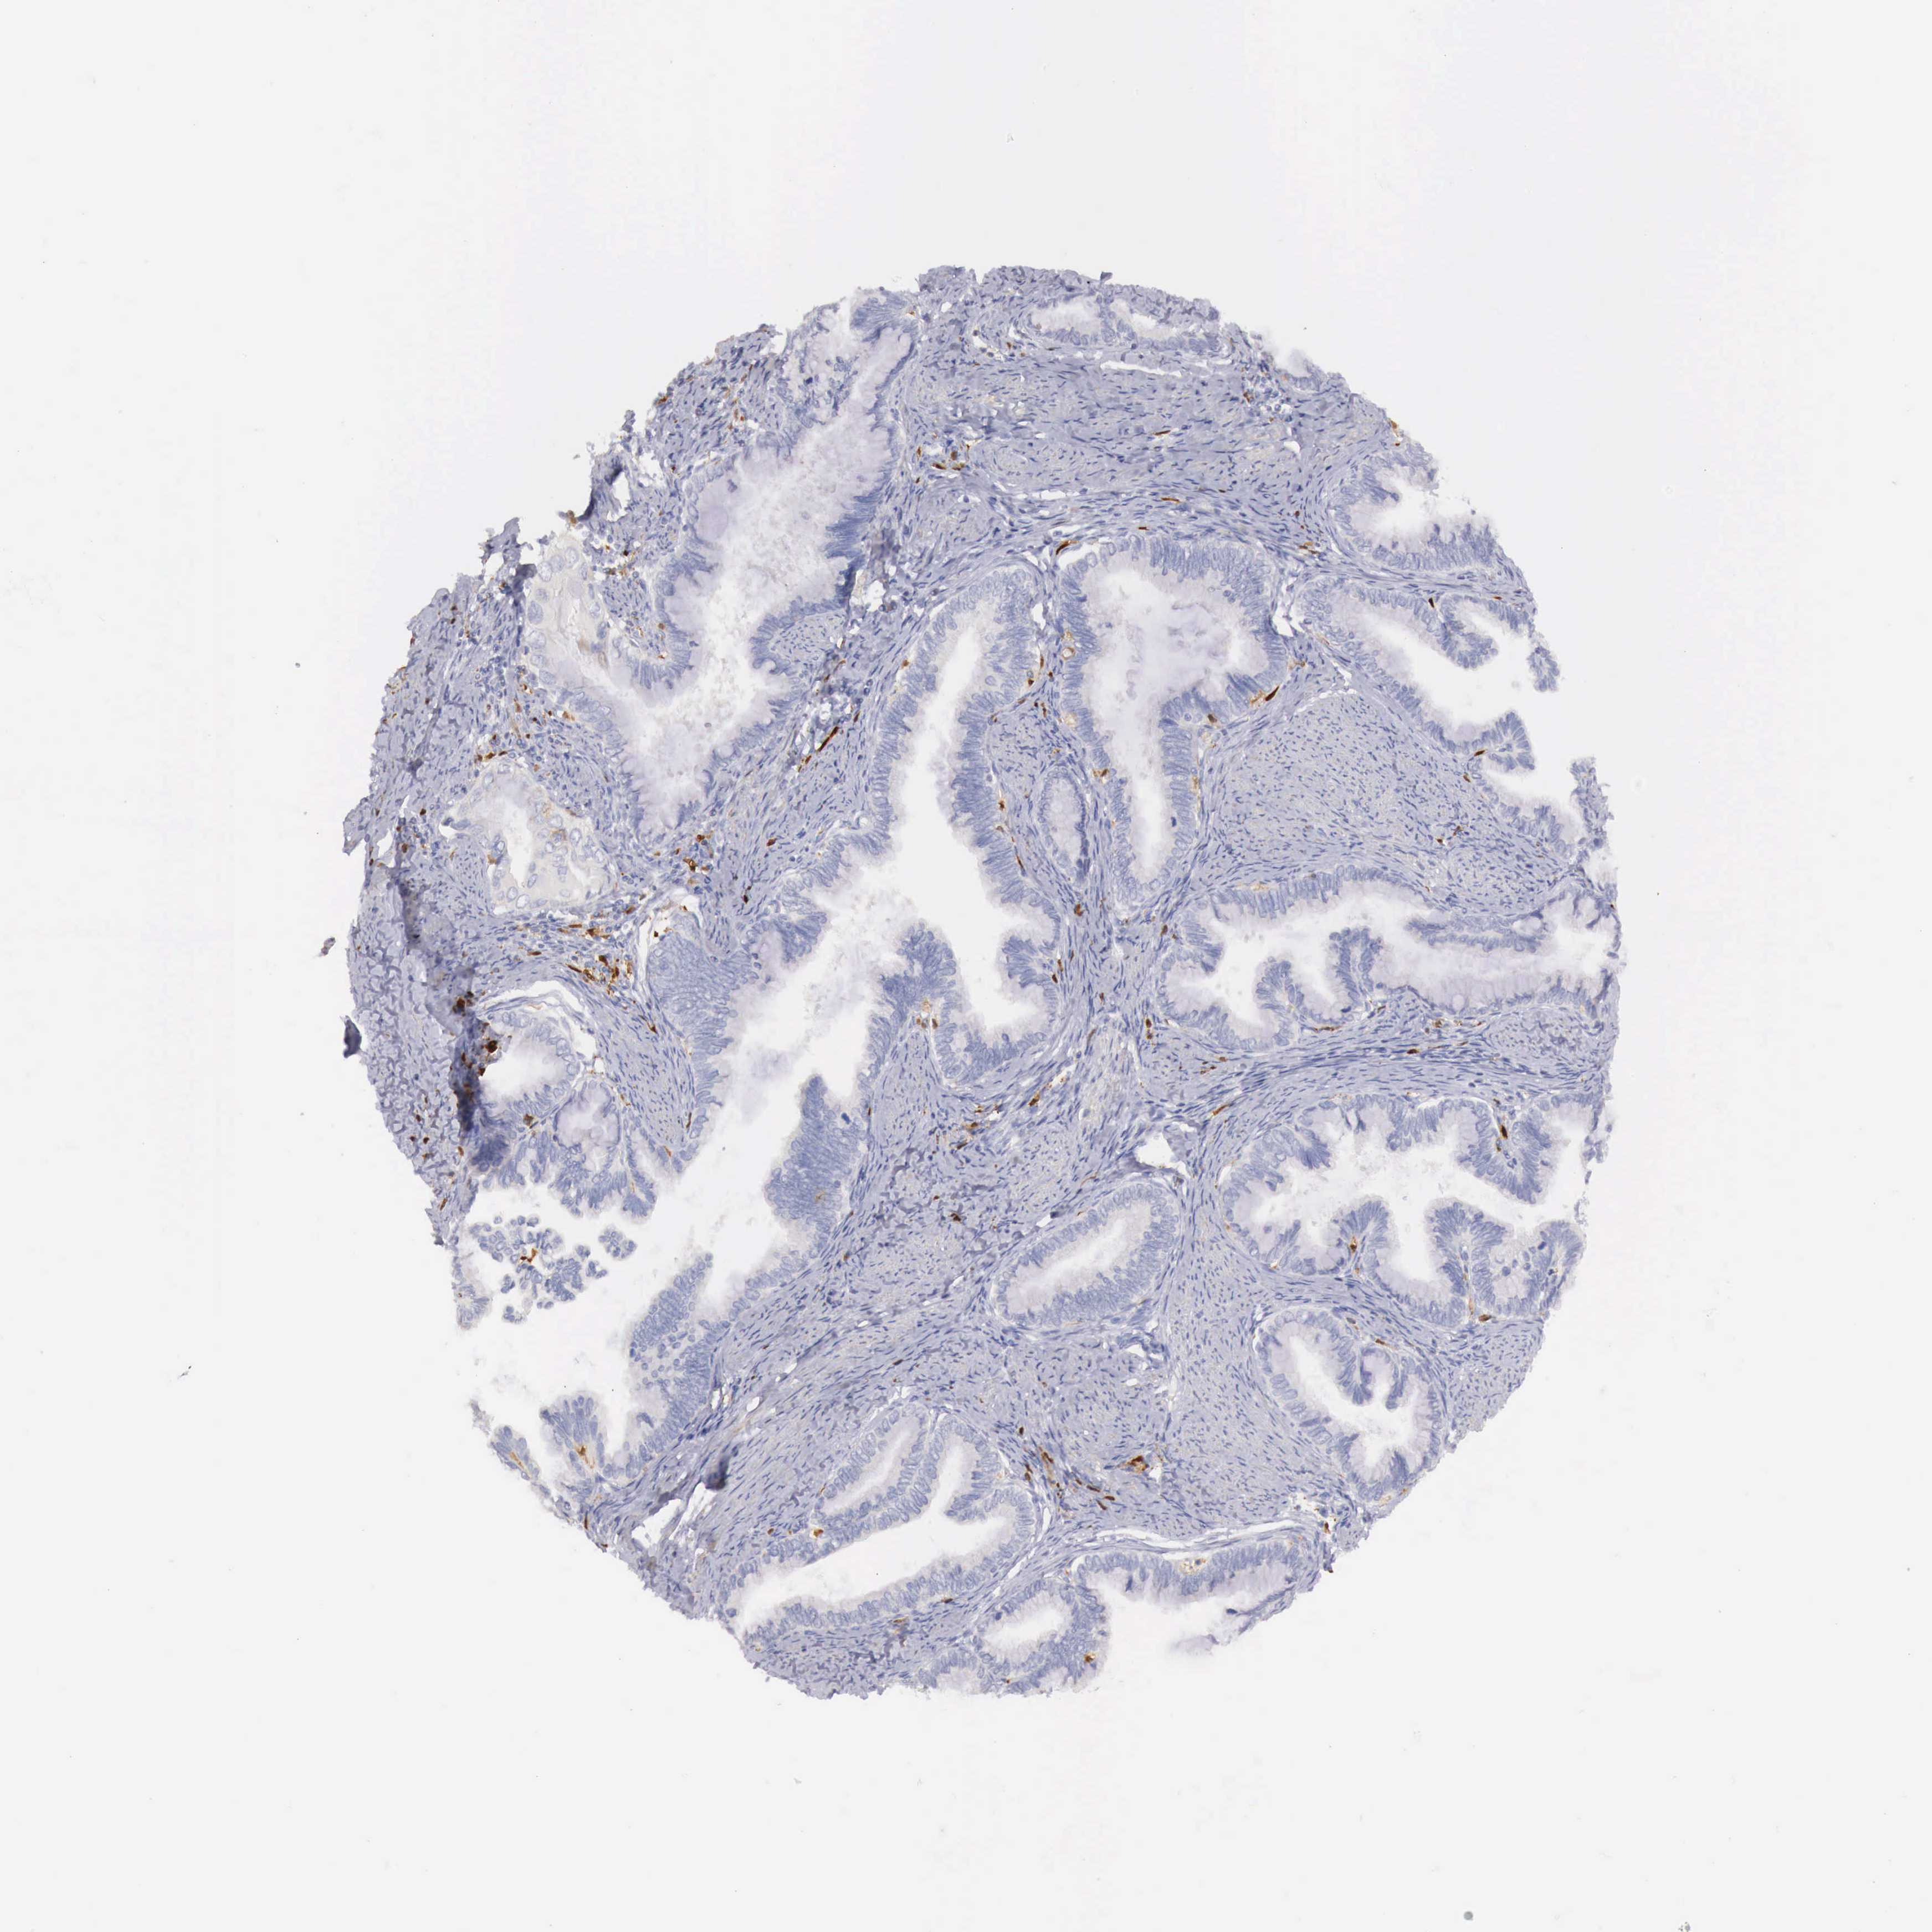

CERVICAL CANCER - Protein expressioni

A mouse-over function shows sample information and annotation data. Click on an image to view it in a full screen mode. Samples can be filtered based on level of antibody staining by selecting one or several of the following categories: high, medium, low and not detected. The assay and annotation is described here.

Note that samples used for immunohistochemistry by the Human Protein Atlas do not correspond to samples in the TCGA dataset.

Antibody stainingi

Antibody staining in the annotated cell types in the current human tissue is reported as not detected, low, medium, or high, based on conventional immunohistochemistry profiling in selected tissues. This score is based on the combination of the staining intensity and fraction of stained cells.

Each image is clickable and will lead to virtual microscopy that enables deeper exploration of all samples and also displays staining intensity scores, fraction scores and subcellular localization as well as patient and tissue information for each sample.

Antibody HPA000428

Antibody HPA000522

Staining

High

Medium

Low

Not detected

Intensity

Strong

Moderate

Weak

Negative

Quantity

>75%

75%-25%

<25%

None

Location

Nuclear

Cytoplasmic/membranous

Cytoplasmic/membranous,nuclear

Adenocarcinoma, NOS

Squamous cell carcinoma, NOS